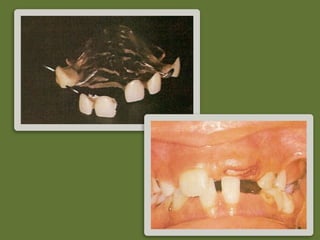

Prótese

Removível

– Indicações:

• Perda

precoce

com

posterior

erupção

maior

que

6

meses.

• Casos

de

Oligodon;a

Requisitos:

Manter

espaço

para

dos

sucessores

Não

interferir

no

processo

desenvolvimento

dentes

e

arcos

dentários.

Impedir

extrusão

do

antagonista

Devolver

função

mas;gatória

Restaurar

contornos

labiais

Fácil

limpeza